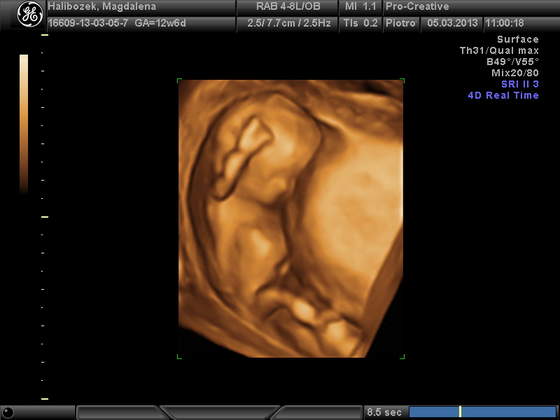

co do płci lekarz na dzisiejszym usg nie chciał się jeszcze wypowiadać twierdząc że to jeszcze za wczesnie i organy meskie/zenskie są do siebie w tym momencie bardzo podobne

ale w piatek jak bylam na kontrolnej wizycie moj lekarz prowadzacy obstawiał dziewczynkę ale to oczywiście nie na 100% :-)